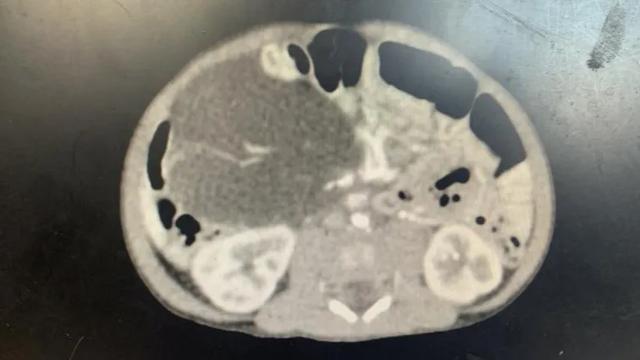

右腹部肿块

近日,一位来自宁德的宝妈带着10天大的黄疸宝宝来到福建医科大学附属福州儿童医院。令人惊讶的是,经腹b超显示孩子左腹部有一个巨大的肿瘤,但CT显示肿瘤位于右腹部。突如其来的变化吓坏了孩子的母亲。肿瘤在哪里?为什么检查结果自相矛盾?

通过对患儿详细的身体检查和CT片的解读,肿瘤外科主任刘升表示,这是一个位于腹腔内的“移动”肿瘤,因为肿瘤位于肠系膜,它会随着肠的肠系膜轴左右摆动。

听了医生的解释,马宝更加疑惑了:新生儿也长肿瘤吗?肿瘤是良性的还是恶性的?我该怎么办?对此,刘升主任解释说,这种肿瘤是肠系膜囊肿,新生儿儿童疾病的病因大多是淋巴阻塞、囊性变和肿瘤改变,多发生在小肠系膜或肠系膜根部。肿瘤多为良性,由无数扩张的淋巴管组成,为大小不等的乳白色囊性结构,直径从几毫米到10厘米不等,多为透明淋巴或乳样乳糜液。目前没有针对囊肿的特效药,以手术治疗为主。